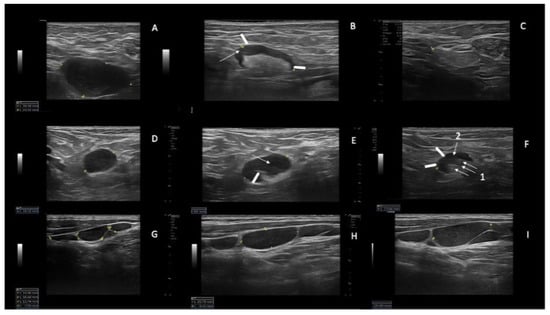

With a median follow up of 12 months (range 6–24 months), we found a nodal (SupLNs and AbdLNS) and splenic response in N = 21/22 patients with 95.4% ORR. We found N = 15/22 (68%) CR, N = 6/22 PR (27.2%), and SD N = 1/22 (4.5%) (Figure 1). We did not detect PD during treatment.

Figure 1.

Examples of SupLNs achieving CR, SupLNs in persistent PR, and SupLN in SD. (A) Right axillary CLL-LN (39 mm × 24 mm) at baseline (T0). The LN appears hypoechoic, with sharp and regular borders, without a visible hilum, L/S ratio < 2, and with a thickened and reticulated cortex. (B) the same LN at T3 (27.3 mm) showing a partial involvement by CLL. The cortex appears inhomogeneous (the anterior part more thickened than the posterior part-white arrowheads, with reticulated cortex-white arrow). The hyperechoic hilum is visible, although irregular. (C) the same LN measuring 19.3 mm, has become liposclerotic (nodal CR) at T6. (D) Right axillary CLL-LN (19 mm) at T0, with round shape (L/S < 2) showing the same US features as for the LN shown in panel A. (E) the same LN at T6 showing a partial involvement by CLL (19.2 mm): US show a visible hilum which is displaced and truncated (white arrowhead 1), the cortex is thickened inhomogeneous, with reticulation (white arrow). (F) the same LN at T15 (13 mm) showing a persistent partial CLL involvement of the LN: the cortex is still not homogeneously thickened, which determines irregular borders of the LN (white arrowheads) and irregular shape of the hilum (white arrow 1) which appears dislocated in the posterior part of the LN. The cortex shows reticulation (white arrow 2). (G) left laterocervical CLL-LN in SD at T0. (H) left laterocervical CLL-LN in SD at T12. (I) Left laterocervical CLL-LN in SD at T24. The SupLNs present “chain”-shaped, contiguous, sharp borders without US visible hilum. The cortex is inhomogeneous and thickened, with reticulation.

Using a high resolution US linear probe, we found that in several SupLNs the echostructure showed features of involvement by CLL present only in a small portion of the LN, which was never described before. This echostructure feature was detected in N = 8 patients (36.3% of our casuistic), and in 4/8 it was a transient US status, because eventually achieved a status of US nodal CR (Figure 1A–C), and accordingly reached a PB-uMRD. Two patients out of 4, with a partial US residual involvement by CLL (Figure 1D–F and Figure 2D–G) attained uMRD.

Moreover, we report on SupLNs with echostructure consistent with a partial involvement by CLL detected with high resolution linear probe. This partial involvement of SupLNs has never been described before in patients affected by CLL. These echostructure features appear to either stabilize into a persistent PR (Figure 1D–F and Figure 2D–G) or appear a transient status turning into a complete nodal CR (Figure 1A–C). This transient change in the echostructure of SupLNs might be explained by a total of ten US examinations (1 at baseline T0, three during combination treatment and six from EoCT until the end of second year).